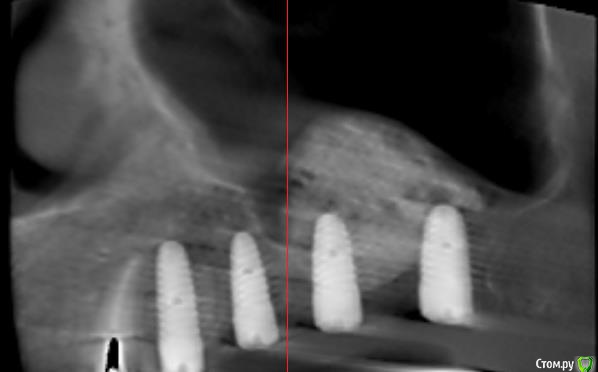

Sergiosse Опубликовано 10 июня, 2017 Поделиться Опубликовано 10 июня, 2017 (изменено) Первый раз делал с приглашенным коллегой, в этот раз сам.Графт церабон 1гр смешал с плазмой и нарезаным сгустком А ПРФ. Хотел делать микст, набрав джейлом ауто с бугра, не получилось, кость как пенопласт. Окно закрыл мембраной АПРФ. Дистальный имплант вкрутил с торком 10 Н\см. Скажу ортопеду чтобы соединил в блок 6 и 7 коронки.Хотелось бы комментариев от опытных коллег все ли сделал правильно? Изменено 10 июня, 2017 пользователем Sergiosse Ссылка на комментарий

Sergiosse Опубликовано 12 июня, 2017 Автор Поделиться Опубликовано 12 июня, 2017 Коллеги,вы бы не ставили 26 , и сделали мостовидный протез с опорой на 14 15 И 17 имплантанты? Какой долгосрочный прогноз выживаемости такой конструкции? Я отказался от этого варианта,так как Кость в обл. 27 мягкая как пенопласт,торк 10Н/см. Считаю ,что рискованно использовать его как опору в мостовидном протезе,и планирую его шинировать с 26, чтобы минимизировать риск перегрузки. К. Миш рекомендуют для Кости 4 класса перед постоянным протезированием ,в течение 4 месяцев давать прогрессивную нагрузку на временных коронках. Ссылка на комментарий